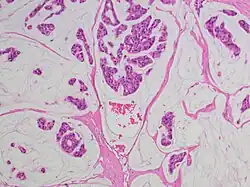

Als Adenokarzinom bezeichnet man einen bösartigen (malignen) von der Deckzellschicht (Epithel) ausgehenden Tumor, der aus Drüsengewebe hervorgegangen ist. Die gutartige (benigne) Zellveränderung von Drüsengewebe nennt man dagegen Adenom.

Adenokarzinome lassen sich im Rahmen der pathologischen Aufarbeitung aufgrund ihrer Gestalt (Morphologie), ggf. Schleimsekretion (Muzingehalt) und Proteinausstattung typisieren sowie teilweise auch dem Ursprungsorgan zuordnen, was insbesondere bei Metastasen wichtig ist, um den Ausgangstumor (Primärtumor) aufzuspüren (vgl. CUP-Syndrom). Zusammengefasst:

- Morphologisch besser differenzierte Adenokarzinome zeigen ein „drüsiges“ Wachstum, z. B. in Röhren (tubulär, azinär, duktal) oder siebförmig (kribriform). Andere Wuchsformen sind z. B. papillär (fingerförmig) und mikropapillär (knospenartig).

- Schlechter differenzierte Adenokarzinome wachsen oft „am Stück“ (solide) oder einzelzellig (diffus) und können ggf. nur mittels Zusatzuntersuchungen von anderen Karzinomen wie z. B. einem schlecht differenzierten Plattenepithelkarzinom unterschieden werden. Mischform: adenosquamöses Karzinom.